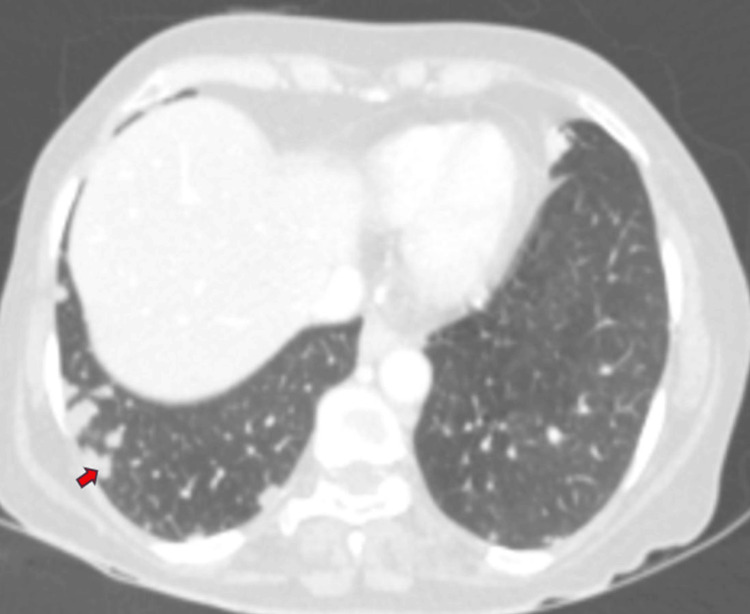

Additionally, multiple well-defined soft tissue density nodular lesions, ranging in size from 2 to 10 mm, were observed in both lower lobe basal segments, predominantly peripheral and subpleural in location, with mild heterogeneous post-contrast enhancement (Figure 8). Visualized bones appeared normal, without evidence of osteolytic or osteoblastic metastases.

Multiple enlarged lymph nodes were noted at various locations, including the porta hepatis, peripancreatic region adjacent to the pancreatic head, celiac region, aorto-caval region, pre-aortic, left para-aortic region, and retrocaval region (Figure 11). These lymph nodes exhibited T1WI hypointensity and T2WI heterogeneous hyperintensity, with central necrotic areas of variable sizes. Some lymph nodes demonstrated diffusion restriction on DWI and appeared coalescent. The pancreas appeared normal. Visualized lower lobes of both lungs exhibited well-defined T2WI hyperintense lesions ranging in size from 2 to 15 mm, with peripheral and subpleural distribution.